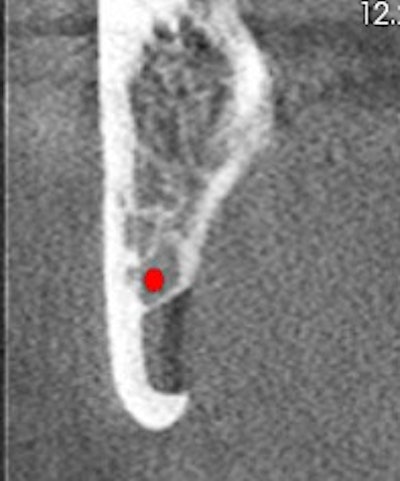

The oral surgeon ordered a cone-beam CT (CBCT) exam. Click images below to enlarge. In order: reformatted panoramic radiograph and cropped image of the area of interest, coronal view of the posterior right mandible (the inferior alveolar canal in red), and 3D reconstructed image of the posterior right mandible.

Figure 3: Coronal view of the posterior right mandible (the inferior alveolar canal is highlighted by red dot).

There is a hypodense lesion (radiolucent) that is well-defined, well-corticated, oval in shape, 8 x 6 mm, located at the posterior right mandible, and distal to tooth #32. The lesion is located below the inferior alveolar canal. No expansion is observed in the cross-sectional views. No calcifications are observed inside the lesion.

From the radiographic perspective, Stafne bone defects are radiolucent lesions, well-defined and well-corticated, oval in shape, and located below the inferior alveolar canal. No expansion is usually observed in the coronal views.

The differential diagnosis includes benign and malignant lesions; however, the location below the inferior alveolar canal is an anatomical landmark that helps to differentiate a Stafne bone defect from odontogenic lesions (usually located above the inferior alveolar canal).